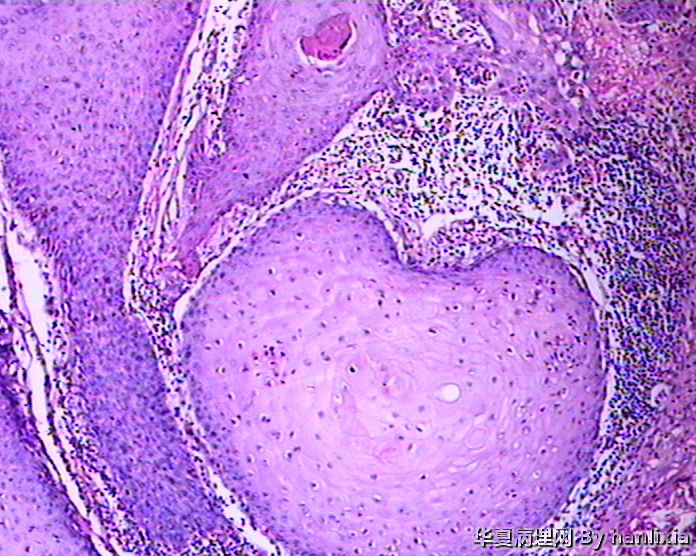

男性患者,50岁,发现面部皮肤(耳旁)肿物一年余,色黑。

高分化鳞状细胞癌

高分化鳞癌可能,也可能AK基础上发展而来的浅表型鳞癌?

部分区域突破基底膜,应该诊断鳞癌,由日光性角化发展过来的!